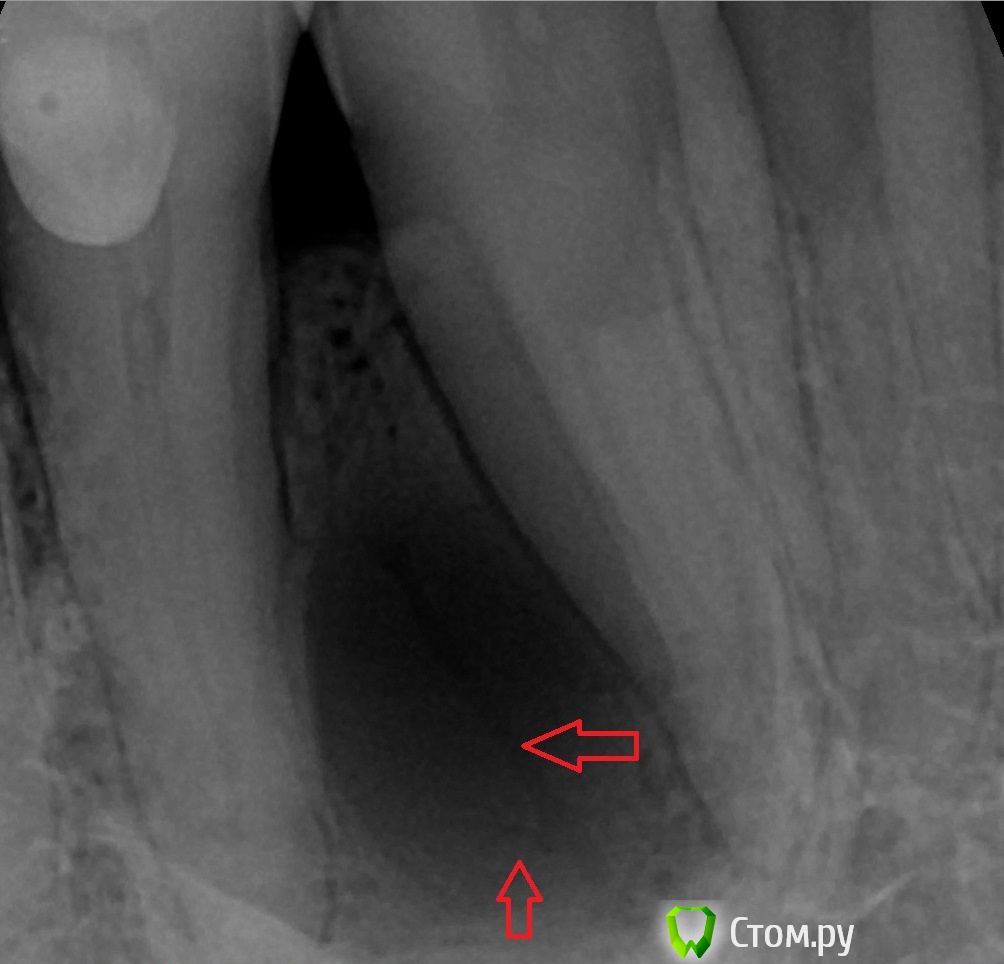

faity Опубликовано 27 мая, 2014 Поделиться Опубликовано 27 мая, 2014 вчера пришел пациент на удаление и имплантацию, а у него такое говорит уже лет 5, то "надувается", то "сдувается". причем в размерах уменьшается при определенных обстоятельствах, со слов пациента: "она когда выростает сильно(ком.авт: на снимке это не сильно, по его параметрам большой размер- когда зубы перестают смыкаться), я литр водки выпиваю- и она сдувается, раз в полгода так примерно и пью" на рентгене вот так думаю биопсию сделать, если не онкогенеза- иссеку и аугментирую, думаю 4.3 и 4.4 не трогать.какие мысли, предложения? 1 1 Ссылка на комментарий

DokDent Опубликовано 27 мая, 2014 Поделиться Опубликовано 27 мая, 2014 А что это в "кисте"? Очень похоже на сосуд 2 Ссылка на комментарий

faity Опубликовано 27 мая, 2014 Автор Поделиться Опубликовано 27 мая, 2014 1. Не важно, любое ксено, возможно и без графта обойтись2. Любая коллагеновая3. Лоскутом4. Проба на витальность до вмешательства - эод и термометрия хладагентом, у меня эндофроста нет, хотя бы ледышку приложить1 я думаю из области вмешательства скребком набрать2 у нас только биогайд закупают, так можно чем угодно, согласен3 язычно пришью, а вестибулярно простолоскутом натянуть? не слетит?4 согласен может на "ты"? давно вроде общаемся, меня Андрей зовут А что это в "кисте"? Очень похоже на сосуд может сосуд, а может линия перелома, вскрытие покажет Ссылка на комментарий